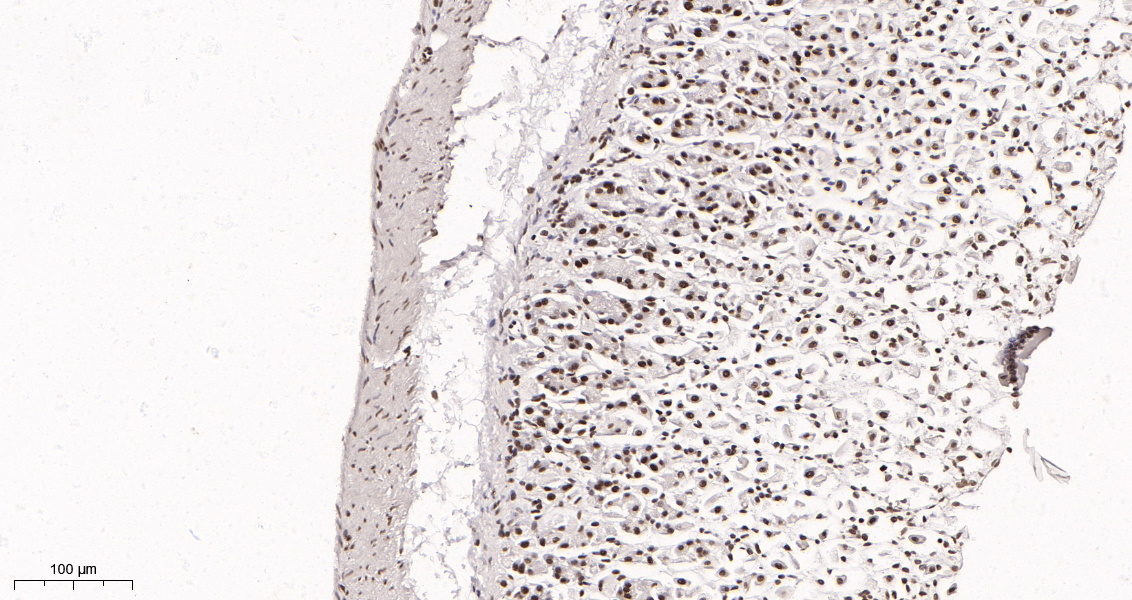

产品名称Rad21 (16H8) Rabbit Monoclonal Antibody

推荐应用WB,IHC-P,IF-P,IF-F,IF-ICC,IP,ELISA

稀释度IHC-P 1:200-1000,WB 1:1000-5000,IF-P/IF-F/IF-ICC 1:200-1000,ELISA 1:5000-20000,IP 1:50-200